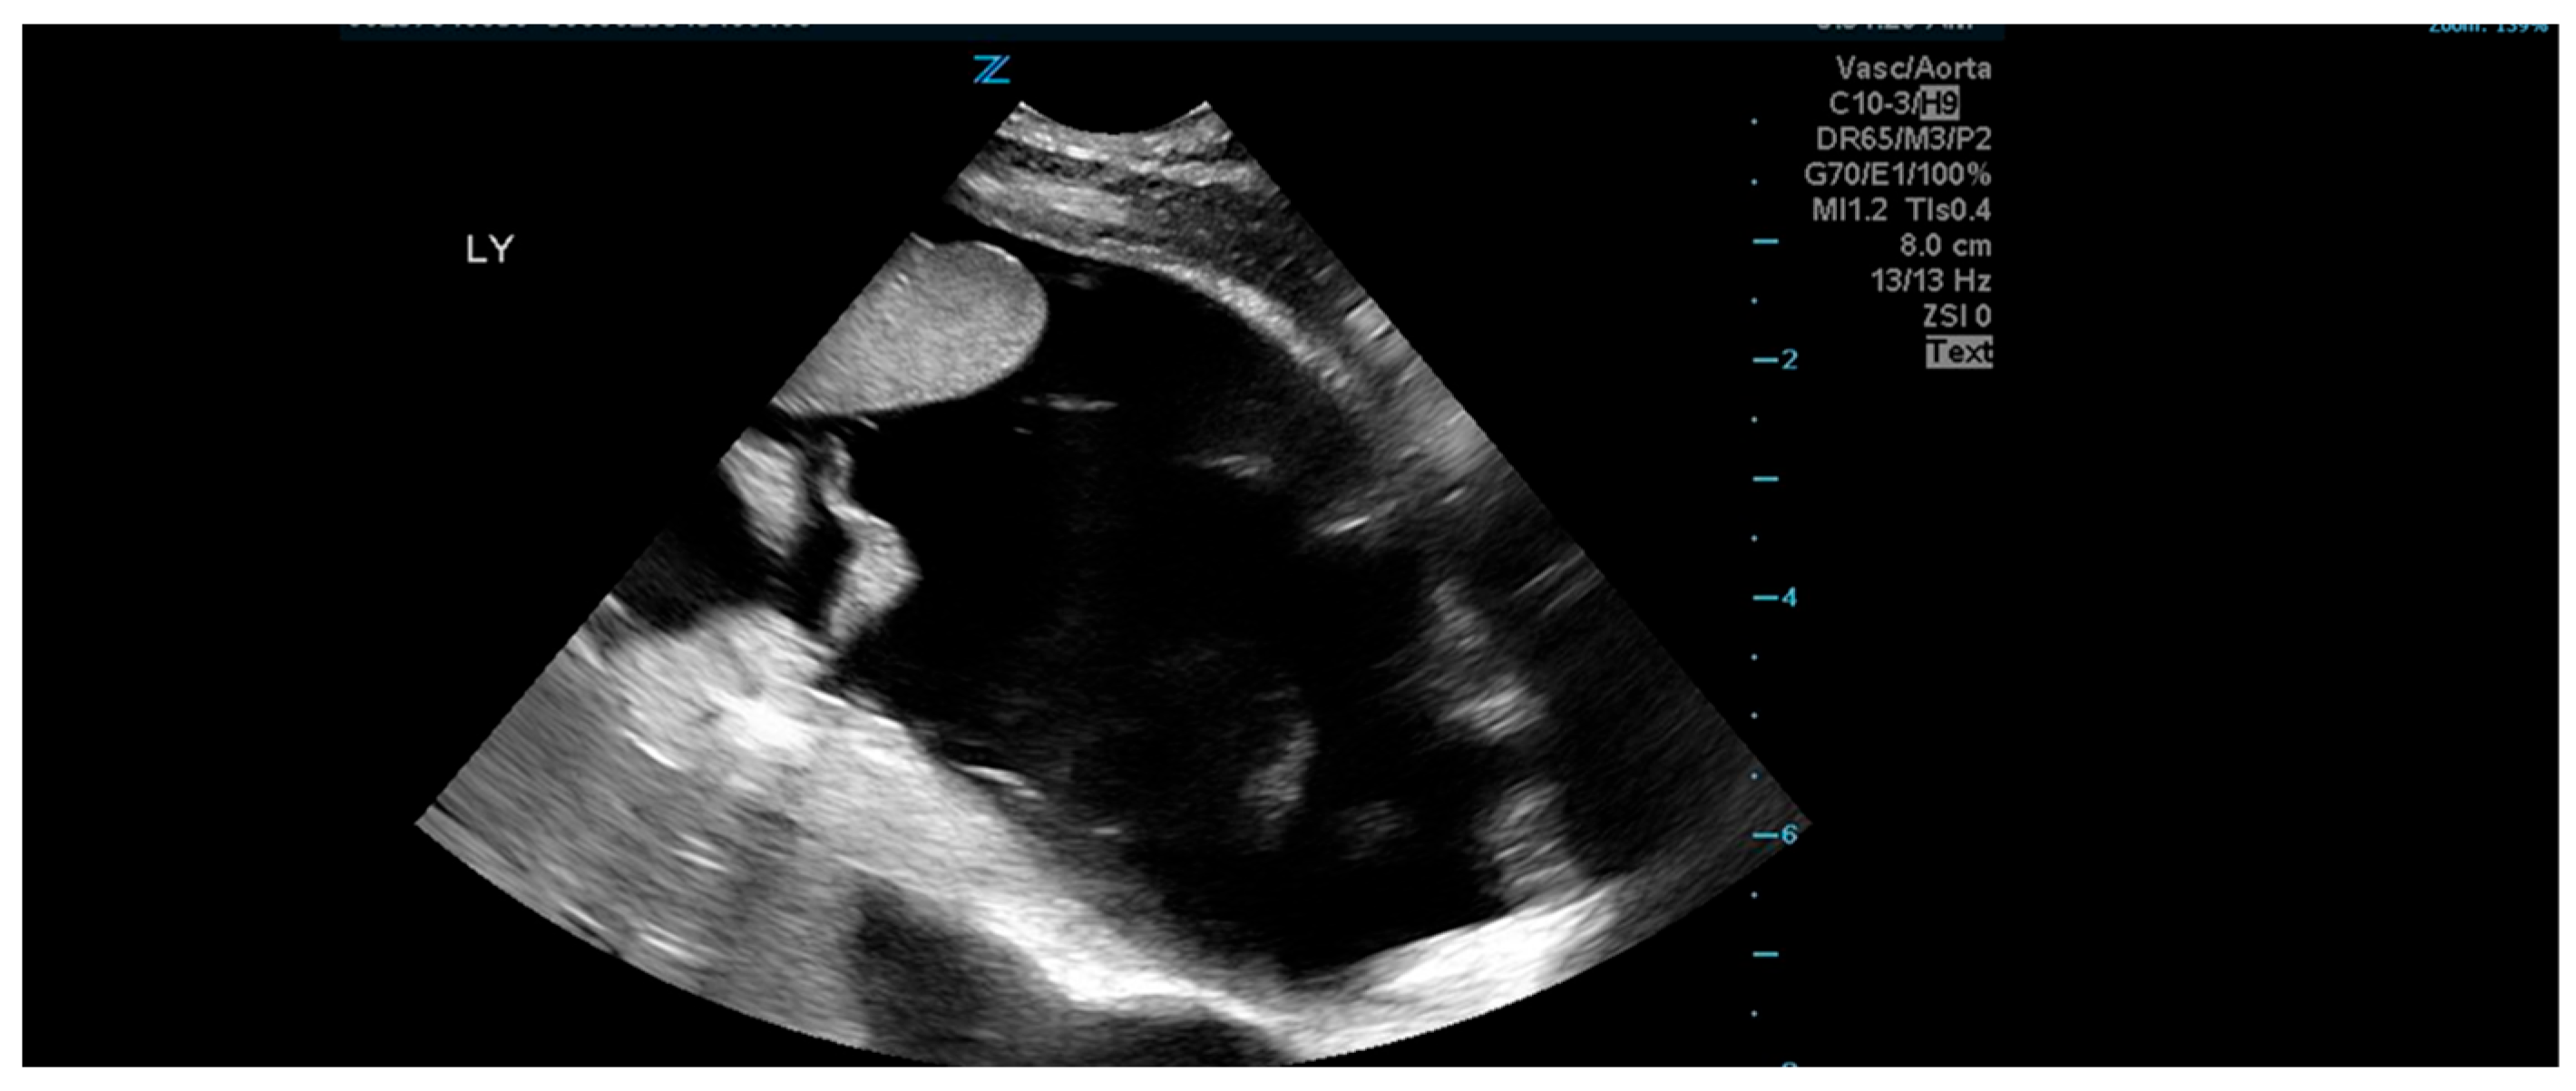

2. Case Presentation